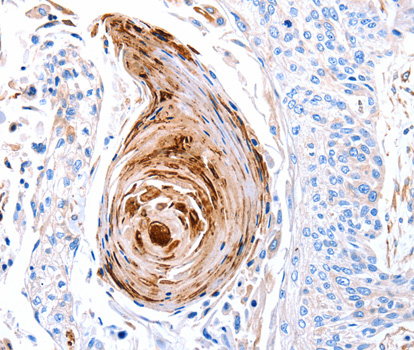

• A2958: image 2

Immunohistochemistry of paraffin-embedded human esophagus cancer tissue using GLRA1 antibody.